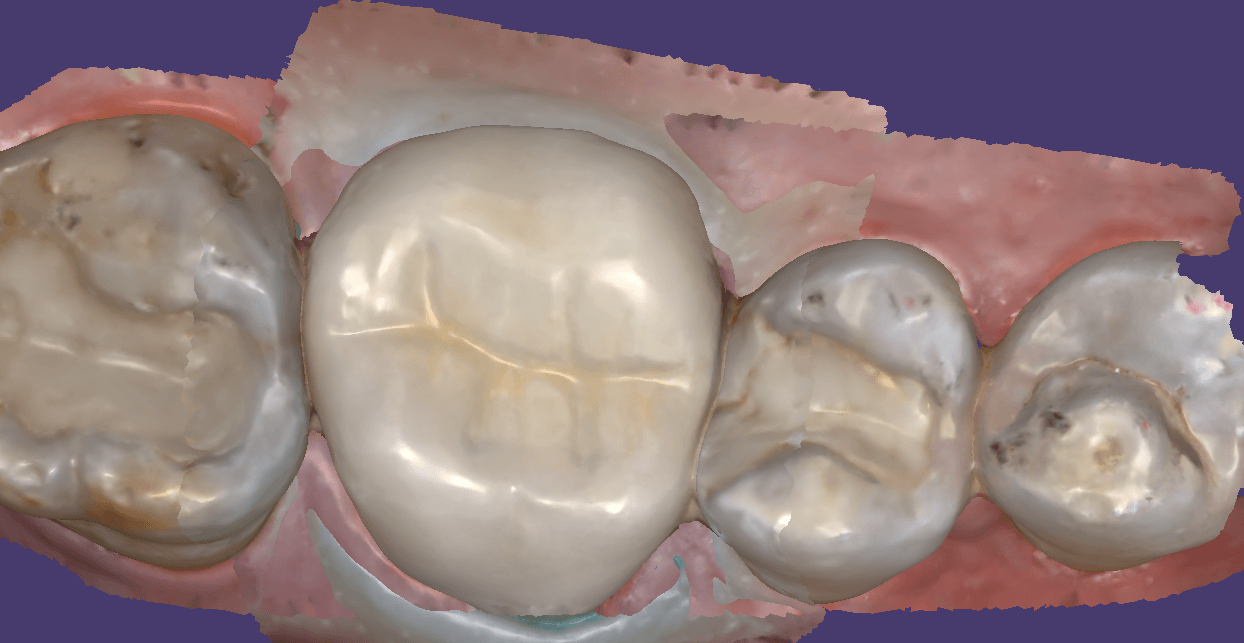

You can scam the opposing (here the upper hybrid was being repaired as the left central incisor had fallen off), scan the denture in place of the appropriate arch, and then you can take the buccal bite.

You can then take the prosthesis out of the mouth and continue imaging it and roll over to the intaglio and capture that information.